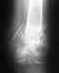

День добрый . Подскользнулся на вело, упал на бок на плечо. В травмпункте сделали гипсовую повязку Дезо. Никаких намеков на операцию не было, даже сказали без смещения.

Сегодня сходил в поликлинику, там врач сходу меня ошарашил, сказал нужна операция, вкрутить на месяц шуруп, иначе возможно рука не будет до конца подниматься. Честно скажу, непосредственно после падения я ее поднимал и еще продолжал ехать на вело, так как не верил в перелом. Подскажите пожалуйста, я запутался, уже даже не уверен по снимку в каком месте перелом и нужна ли операция. Спасибо.http://g.io.ua/img_aa/large/1285/30/12853074.jpgфото снимка без гипса